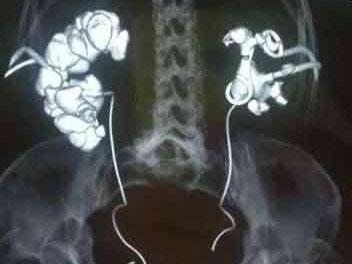

Миниатюризированная перкутанная нефролитотрипсия

Этот метод широко используется в НИИ урологии и интервенционной радиологии имени Н.А. Лопаткина для удаления большинства крупных и множественных камней почек с минимальным риском развития осложнений. При работе этим инструментом используется самый современный гольмиевый лазер большой мощности, способный быстро превратить камень в песок. Данная методика является малотравматичной (диаметр прокола около 5 мм), прекрасно переносится пациентами (минимальная болезненность и дискомфорт) и является высокоэффективной при лечении мочекаменной болезни. Особенности технологии позволяют проводить вмешательство без оставления наружного нефростомического дренажа.

Выполненный через прокол кожи ход в почку надежно закрывается специальным матриксом, пломбирующим канал и содержащим мощные кровеостанавливающие факторы. Таким образом обеспечивается минимальный риск кровотечения и других осложнений. Пациенты быстро восстанавливаются в послеоперационном периоде и могут вернуться домой уже на 2-3 сутки.

Самые сложные камни почек – коралловидные, занимающие все отделы собирательной системы эффективно и быстро удаляются в клинике НИИ урологии и интервенционной радиологии имени Н.А. Лопаткина с использованием патентованной авторской методики бипортальной перкутанной нефролитолапаксии, которая не имеет аналогов в мире. В ходе операции два хирурга одновременно работаю с камнем через миниатюрные доступы, обеспечивая синергический эффект. Таким образом, на 40% сокращается время операции, обеспечивается низкое давление жидкости внутри почки, в 2 раза снижается риск осложнений. Пациенты получают высокие шансы на полное избавление от сложного камня без длительного лечения с применением повторных операций и дополнительных методов разрушения камня.